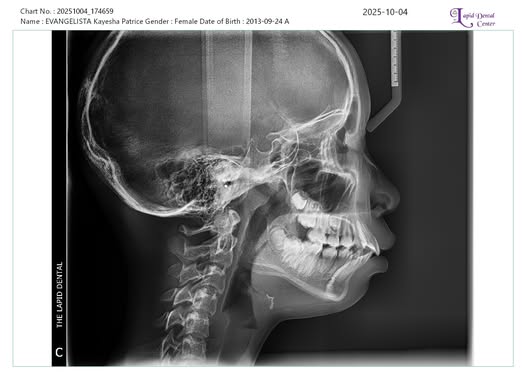

Edit Record Check our patient data records. Add patient information Patient Info Profile picture Last Name First Name Middle Name Birthdate Age Street Barangay City Country Zip Code Contact number Email Procedure 10/04/25 OP 3D SCAN DP FOR ORTHO BAL.2,499.50 ***FOR LC 16(O,L) 36,46 (O,B) 10/10/25 install brace - MBT 0.22 14 NITI U/L Occlusal pads on #36 & #46 Lip tie - level 3 Tongue tie - level 4 11/8/25 Adjustment reattach #36, 35 12/10/2025 Adjustment 16 NiTi U/L New bracket attachment - #35, #45 Molar band #36, #46 01/10/26 adjustment 3/7/26 adj. same wire 16 niti U|L Re-attached #16 Fox 3.5 04/15/26 Adjustment EXO #54 05/09/26 adjustment rabbit 3.5oz (class II) 18 niti U/L File kayesha_panoramic_x-ray.jpg File 2 File 3 File 4 File 5 File 6 File 7 File 8 File 9 File 10 File 11 File 12 File 13 File 14 File 15 File 16 File 17 File 18 File 19 File 20 Retain Record Retain Record Yes No Save Your Changes